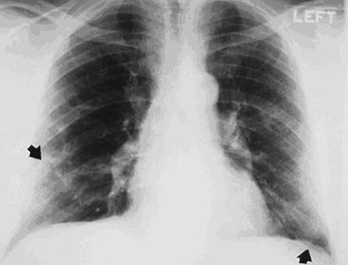

Aparência da silicose à radiografia torácica: existem pequenas opacidades arredondadas, começando inicialmente nos lobos superiores e, com a evolução, esses nódulos menores se conglomeram e formam opacidades grandes (fibrose maciça progressiva). Diferentemente da exposição aos asbestos, não há alterações pleurais observadas na radiografia torácica, embora a fibrose pleural possa ser observada em um espécime patológico da silicose.

Alguns pacientes com exposição a asbestos e sílica podem mostrar alterações radiográficas e/ou patológicas de poeira mista.[Figure caption and citation for the preceding image starts]: Radiografia torácica mostrando alterações consistentes com a silicose simples ou a pneumoconiose dos trabalhadores do carvãoDo acervo pessoal do Kenneth D. Rosenman, Michigan State University [Citation ends].